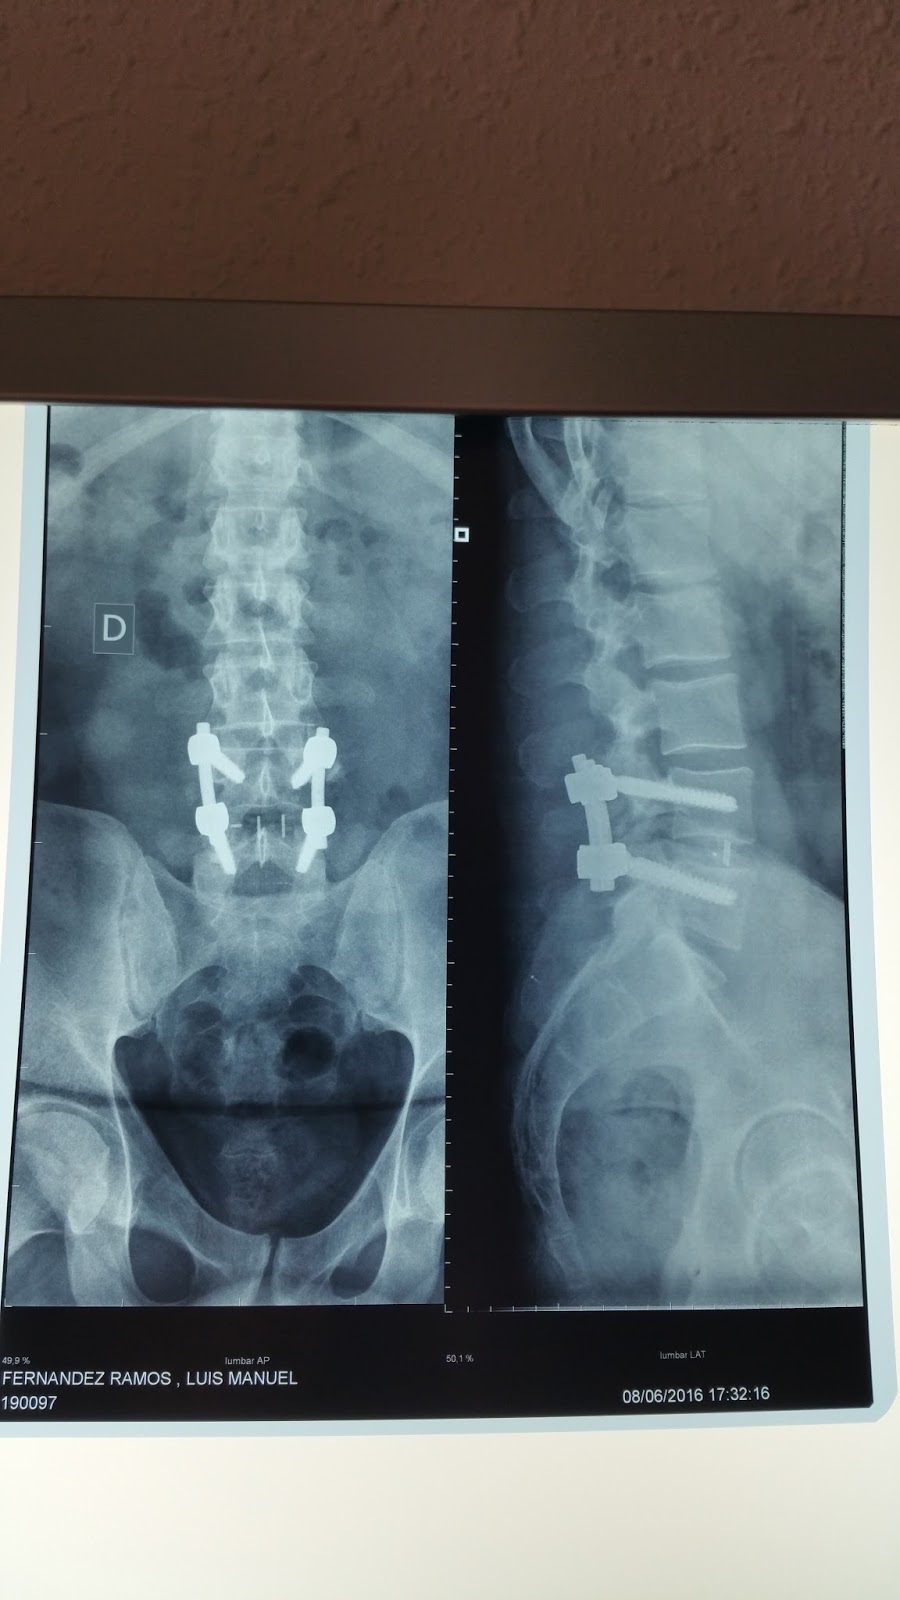

WebLas secuelas que tendremos que tener en cuenta, por tanto, en una artrodesis espinal según la Ley 35/2015, serían las siguientes: Material de osteosíntesis. WebUna paciente con fijación lumbar L5-S1 comenzó con lumbociática izquierda de 5 o 6 meses de evolución con sensación de calambre y déficit motor distal leve. Las pruebas.

WebRM realizadas indicaron protusiones-hernias en L4-L5,L5-S1,y la última mostró discartrosis moderada con protusion posterocentral moderada y compromiso. WebEsto nos hace ver que la artrodesis vertebral solo se realiza en los casos más graves, siendo muy probable que antes de la operación hayamos padecido una serie de dolores.